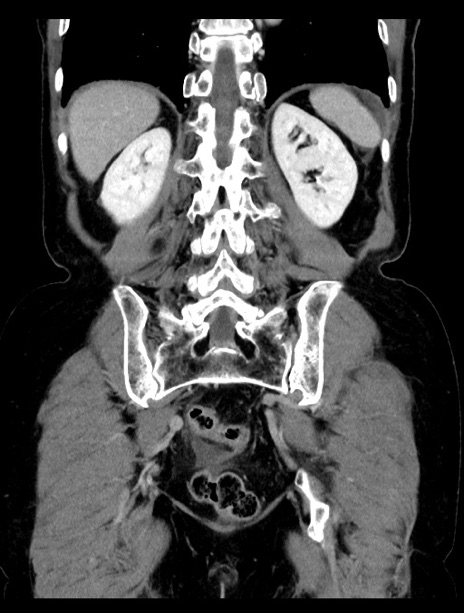

症例23(冠状断像)

【症例】70歳代女性

【主訴】下腹部痛・嘔吐

【現病歴】2日前より腹痛あり。昨日嘔吐あり。症状改善しないため来院。

【既往歴】胃GISTに対して胃部分切除後。

【身体所見】BT 37.1℃、BP 128/77mmHg、腹部:平坦・軟、下腹部に圧痛あり。

【データ】WBC 10200、CRP 0.31